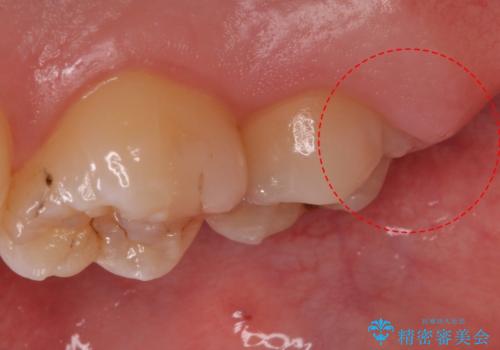

- コンタクトスポーツをするためマウスガードを作りたいとのことで来院された患者様です。

色とマウスガードのタイプをお選びいただけます。